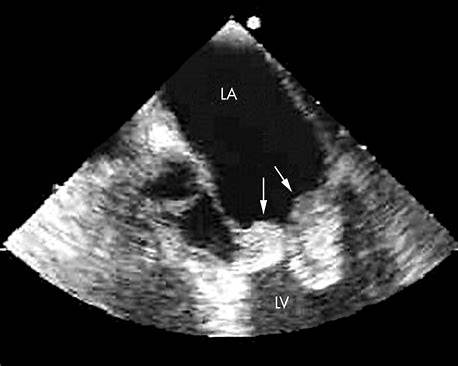

Essential investigations include multiple blood cultures before antibiotics, echocardiography (TTE followed by TEE if needed), inflammatory markers, urine analysis, and imaging for embolic complications.

TEE has higher sensitivity than transthoracic echocardiography, especially for detecting vegetations on prosthetic valves, periannular abscesses, and small lesions.